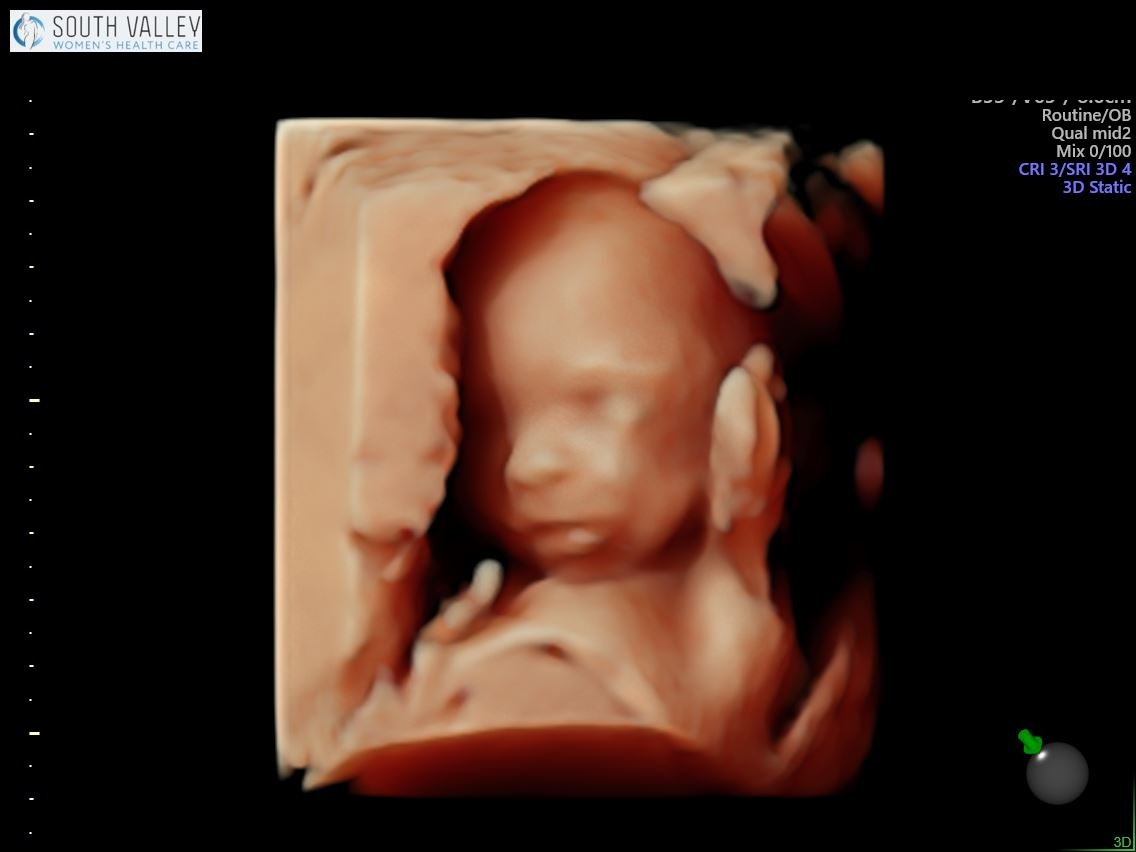

Yesterday we had our anatomy scan and it went well! Everything is looking perfect so far — the brain, the heart, all of those internal organs are in the right place and best of all, I got to see some of he sweetest shots of his cute little face! If you’ve ever wondered what a 19 week old baby in pregnancy looks like, here you have it. She said it’s rare that she gets a face shot this good at such an early age so I was pretty happy about that!

19 Week Ultrasound